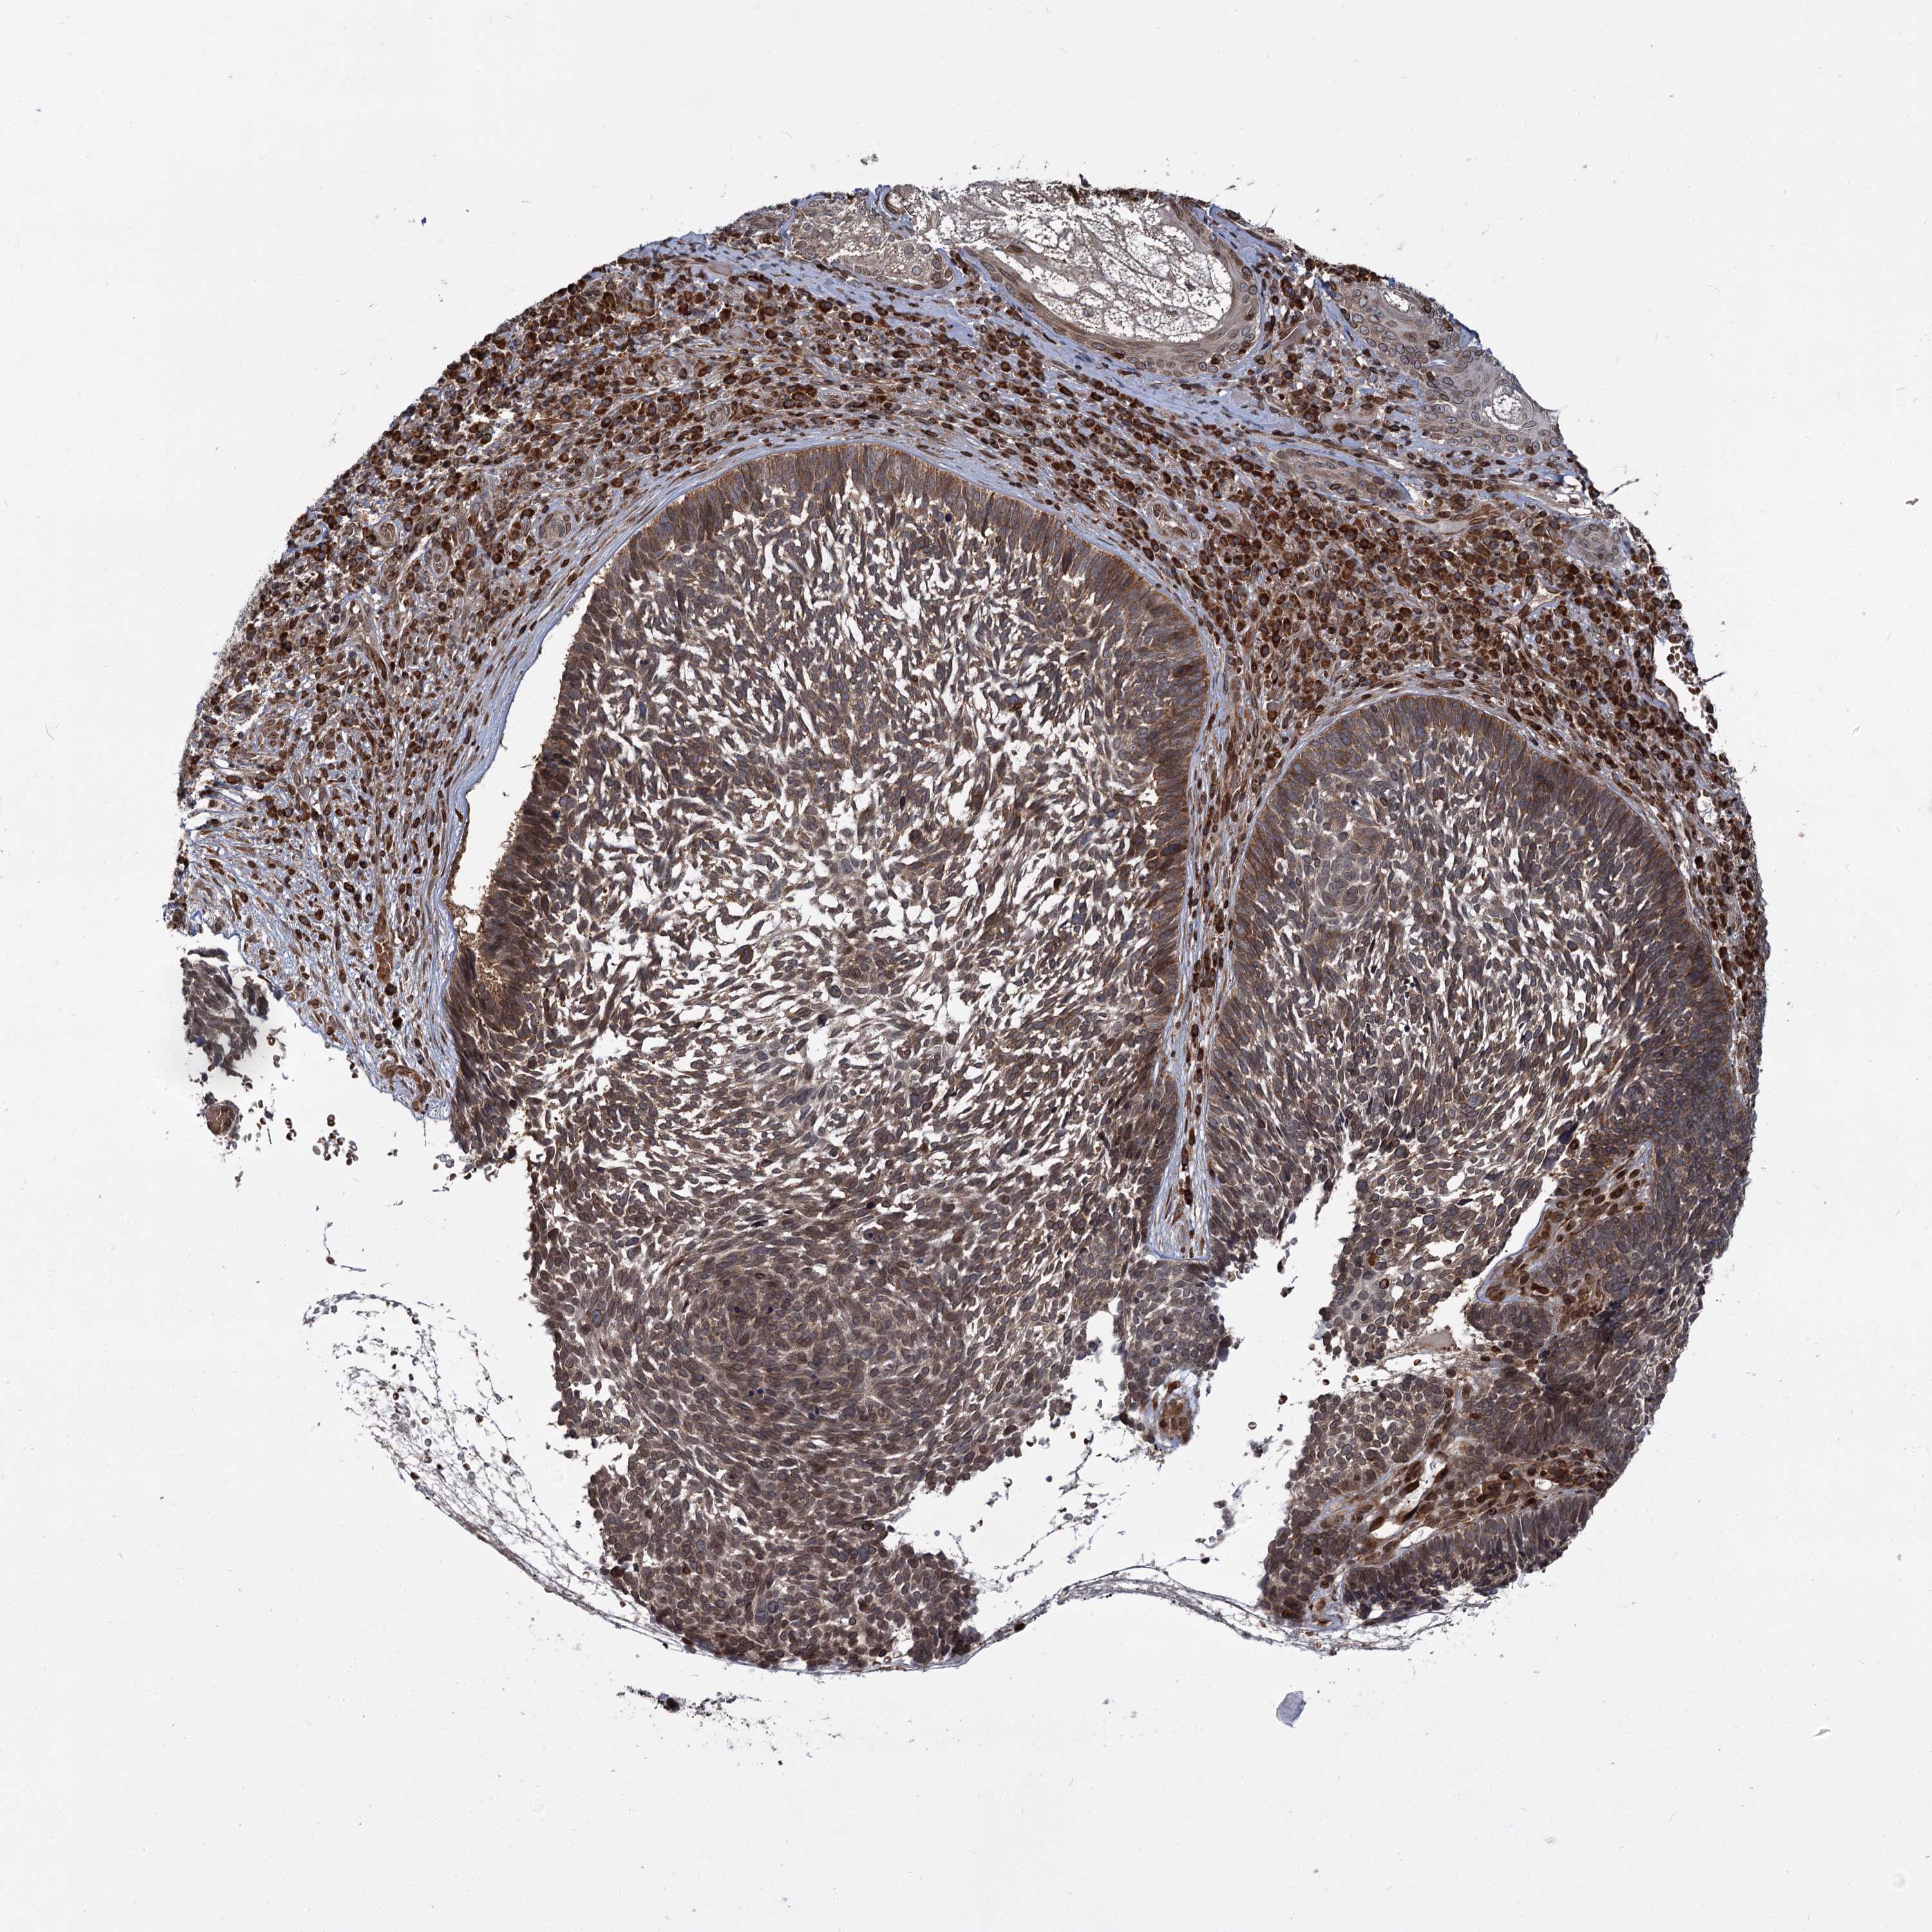

SKIN CANCER - Protein expressioni

A mouse-over function shows sample information and annotation data. Click on an image to view it in a full screen mode. Samples can be filtered based on level of antibody staining by selecting one or several of the following categories: high, medium, low and not detected. The assay and annotation is described here.

Each image is clickable and will lead to virtual microscopy that enables deeper exploration of all samples and also displays staining intensity scores, fraction scores and subcellular localization as well as patient and tissue information for each sample.

Antibody HPA038034

Squamous cell carcinoma, NOS